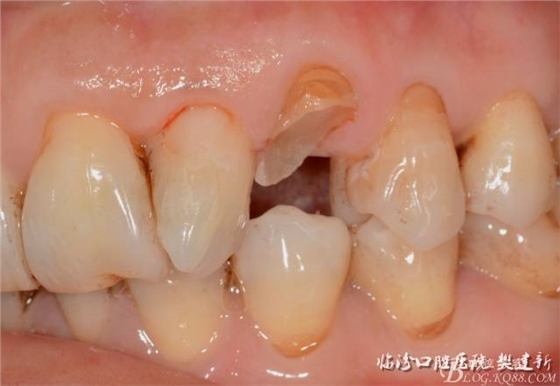

口內(nèi)檢查: 23殘根,位于齦上3MM,根管口探無(wú)反應(yīng),叩(+-),無(wú)松動(dòng),牙周無(wú)紅腫.X片示:23根管無(wú)阻射,根尖骨密度降低.11.12.13頸部楔形缺損,探敏感,牙髓活力正常.全口牙結(jié)石色素(+).

圖123口內(nèi)修復(fù)前情況:殘根位于齦上3MM,牙周無(wú)紅腫.